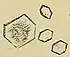

Calcium oxalate crystals can come in two varieties. Calcium oxalate monohydrate can appear as 'dumbbells' or as long ovals that resemble the individual posts in a picket fence. Calcium oxalate dihydrate have a tetragonal "envelope" appearance.[75]

Uric acid stones appear as pleomorphic crystals, usually diamond-shaped. They may also look like squares or rods which are polarizable.[75]